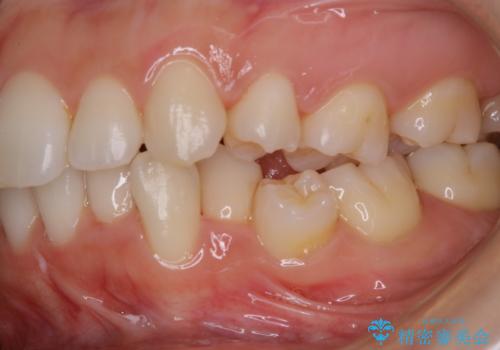

- しばらく来院できなかったため、全体的にチェックとクリーニング希望でした。PMTC60分コースを行いました。

歯にステイン(着色)や歯石などが付着していると、汚れなのか虫歯なのかの判別が分かりにくく、正確な診断ができないことがあります。

そのため、定期的に専門的な機械や材料を使用したクリーニング(PMTC)をすることで、ご自身本来の歯の状態となります。より、健康なお口の維持をするためには、痛みや症状などが無くてもPMTCを行いお口の中の環境を綺麗にすることがおすすめです。